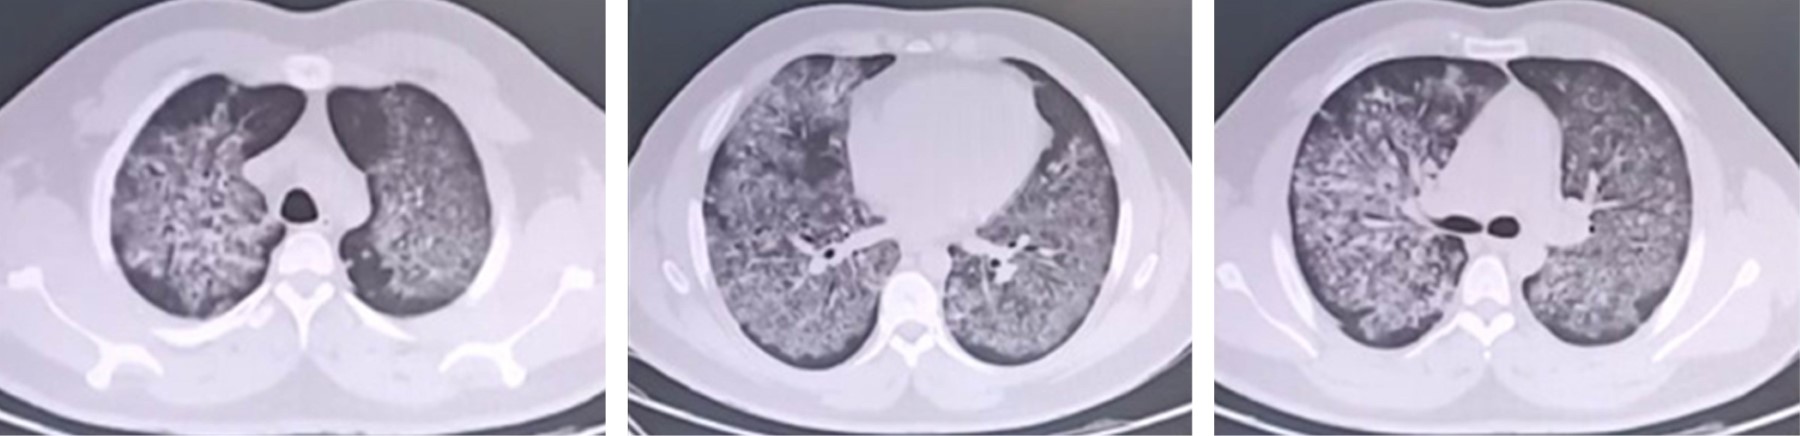

Hemorragia alveolar difusa asociada a E-VALI: revisión de la literatura y reporte de un caso en México

López-Fermín, Jorge1,2; Pérez-Nieto, Orlando Rubén1,2; Deloya-Tomas, Ernesto1,2; Carrión-Moya, Jorge1; Castillo-Gutiérrez, Gabriela1; Olvera-Ramos, María Guadalupe1; de la Torre-Rittscher, Andrea Guadalupe1; Mondragón-Labelle, Tania Olga1; Pozos-Cortés, Karen Pamela1; Trejo-Osornio, David Alejandro1; Zamarrón-López, , Eder Iván2,3; Secchi-del Río, Roberto1